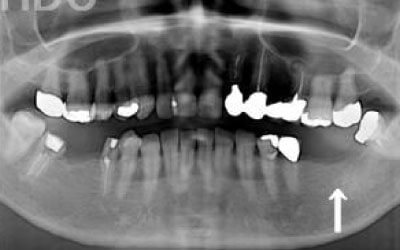

CTでは骨や歯の状態などを3次元で見ることができ、正確な距離を測ることも可能です。

骨の厚みや傾き、神経の位置などを事前にしっかり計測することで安全なインプラントが可能となります。

2 神経を傷つけるリスク

顎の骨の中を通っている神経を傷つけるリスクがあります。

ただ、事前にしっかりCT撮影して三次元的に神経までの距離を計測して治療計画を立てれば心配することはありません。

今回のご質問ですが、抜けた部分の骨が薄いなどの理由で「インプラントはできない」と言われた可能性があります。

前歯はもともと骨が薄く、歯が抜けると時間の経過とともにさらに骨が痩せてきてしまうので、インプラント治療の難易度が高い場所です。

4)骨の状況をしっかり把握するためにも、CT撮影が必須となります。